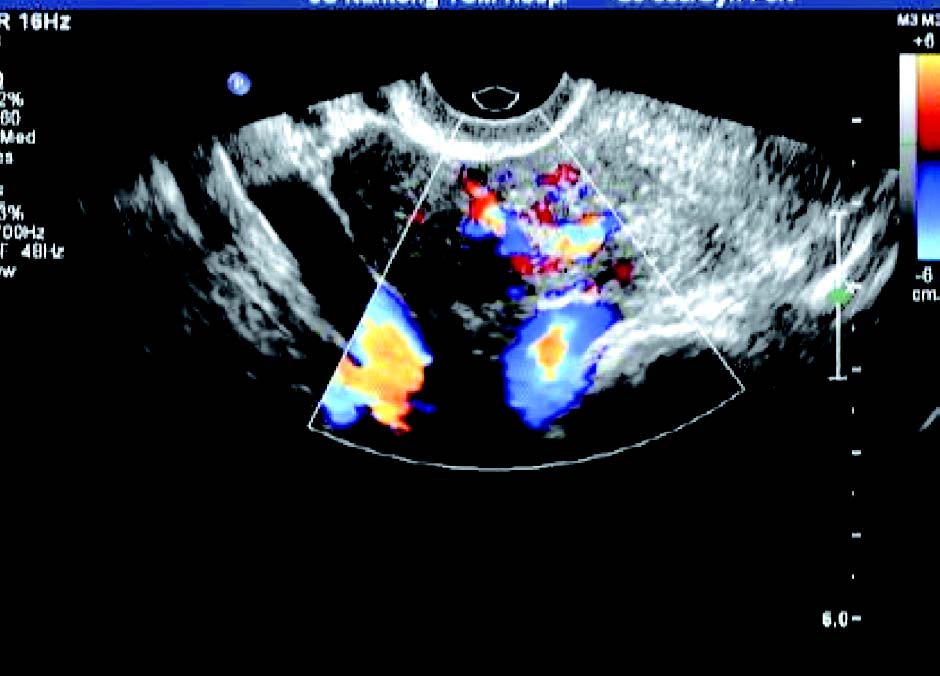

子宫内膜变形或缺损,内膜下肌层可见低回声结节突向宫腔,肌瘤完全突入宫腔时,宫腔内显示实性占位,但肌瘤与宫腔内膜间有裂隙,呈现“宫腔分离征”。CDFI 检测:瘤体周边呈环状或半环状血流信号,内部呈条状血流信号。

经典病例

患者,女,42岁,常规体检。超声检查声像图显示:子宫前位,三径正常,边界清,子宫内膜欠清。肌内可见多个低回声包块,较大者约1.7cm×1.4cm(前壁)、1.8cm×1.4cm(前壁)、1.9cm×1.4cm(后壁),边界清,有假包膜,内部回声均匀,子宫边界规整。CDFI探查:较大团块周围见半环状彩色血流信号。包块内未见彩色血流信号。宫腔内可见节育器影像,距宫底约1.5cm。

超声提示:子宫肌瘤(肌间);宫内节育器,位置正常。